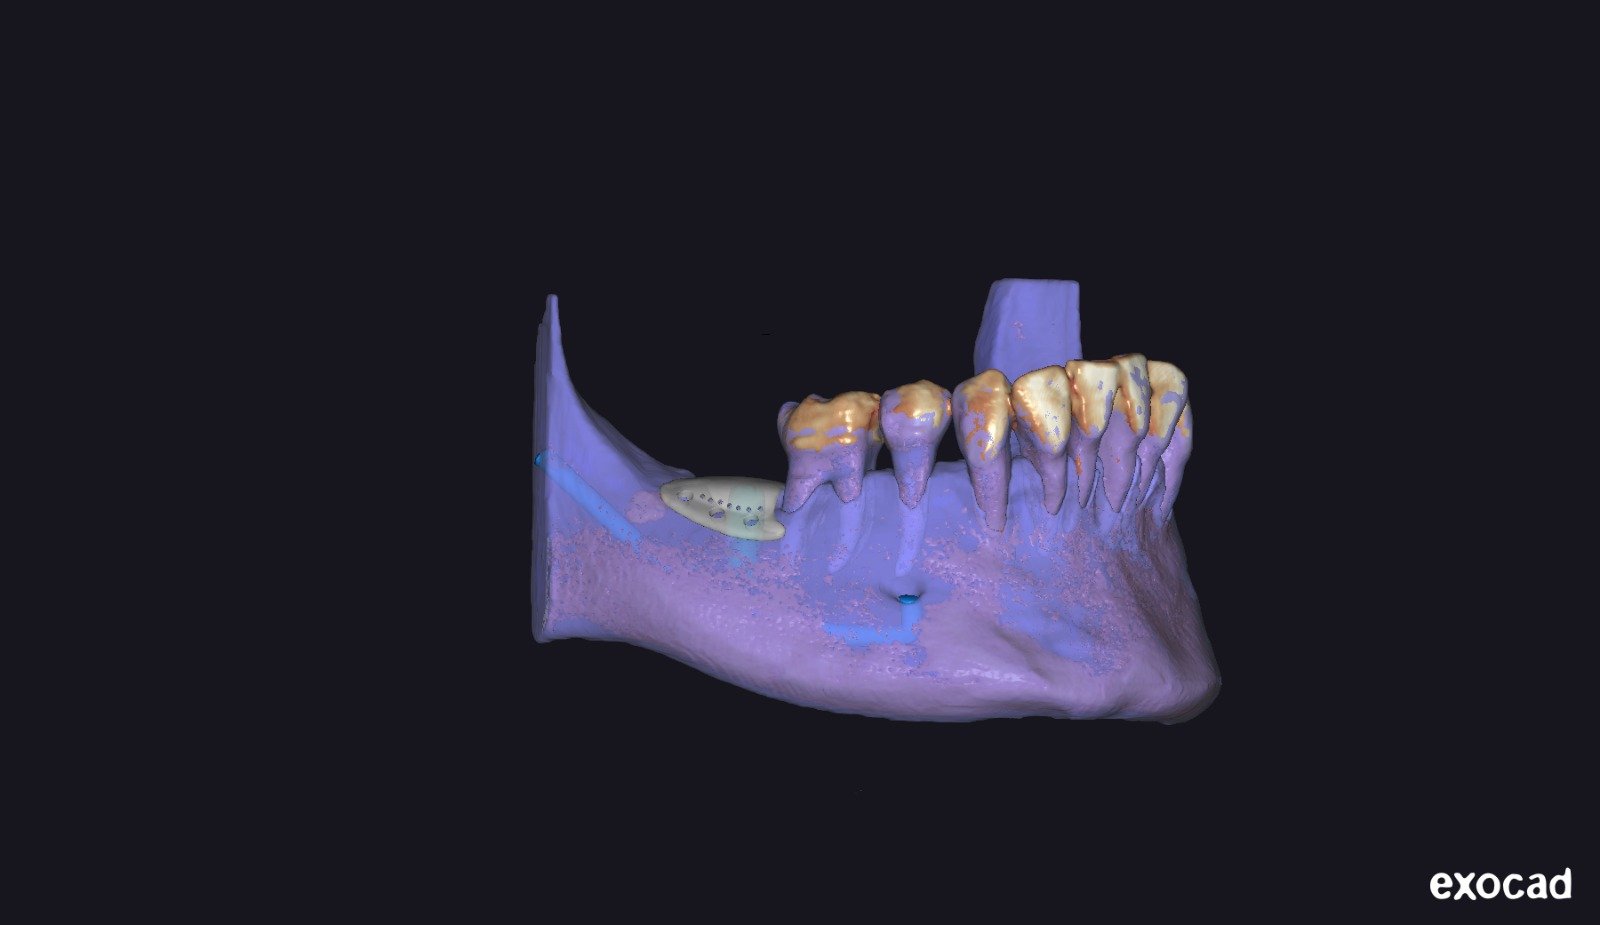

• Exoplan / Exocad: diseño digital aplicado a la regeneración.

• Segmentación ósea y dental.

• Generación del defecto virtual.

• Control tridimensional del volumen a regenerar.

• Concepto de barrera personalizada.

• Principios de diseño biomecánico.

• Espesor, extensión y bordes de la barrera.

• Diseño pasivo y adaptación milimétrica.